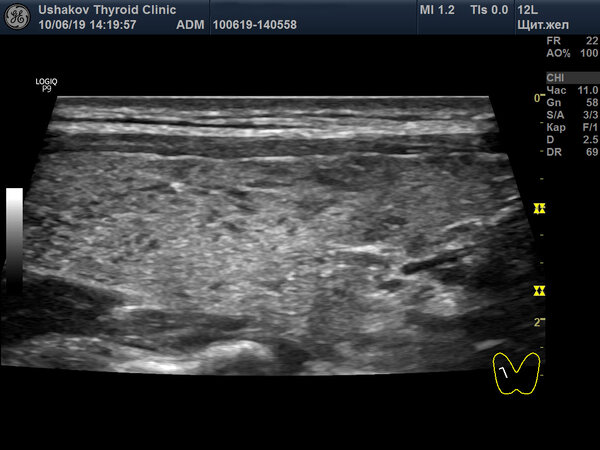

Теперь оцените состояние той же доли через 10 месяцев, на снимке от 10 июня 2019 года.

Структура ткани правой доли стала заметно более однородной. Участки с избыточной лимфоидной инфильтрацией значительно сократились. Достоверность сравнения подтверждается идентичностью подкожных слоёв и общей архитектоники железы на обоих снимках. Все предоставляемые клиникой данные абсолютно достоверны и могут быть проверены.